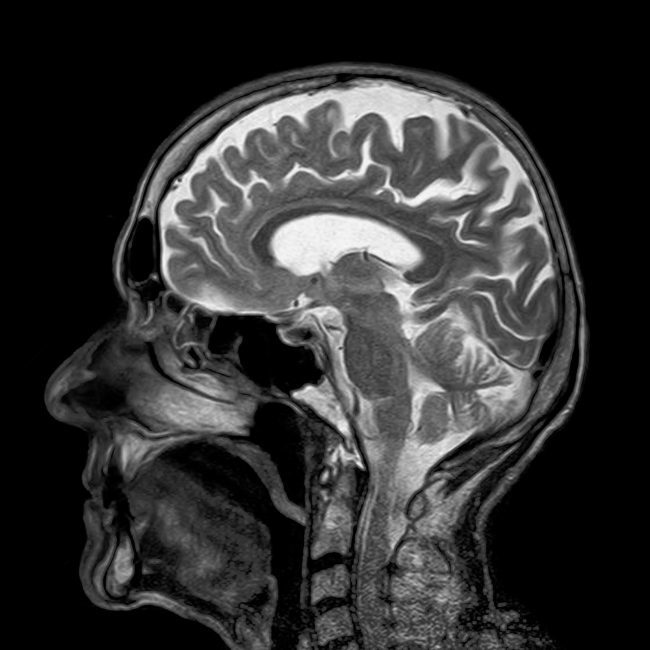

L’ostéopathie après une commotion cérébraleÀ propos de la commotion cérébrale Lors d’un traumatisme violent, le corps est victime d’une onde de choc faisant pénétrer à l’intérieur de celui-ci une grande quantité d’énergie. Si son intensité est trop élevée il s’ensuivra des dégâts importants au niveau de certaines structures ou organes. L’intérêt de l’ostéopathie est donc…